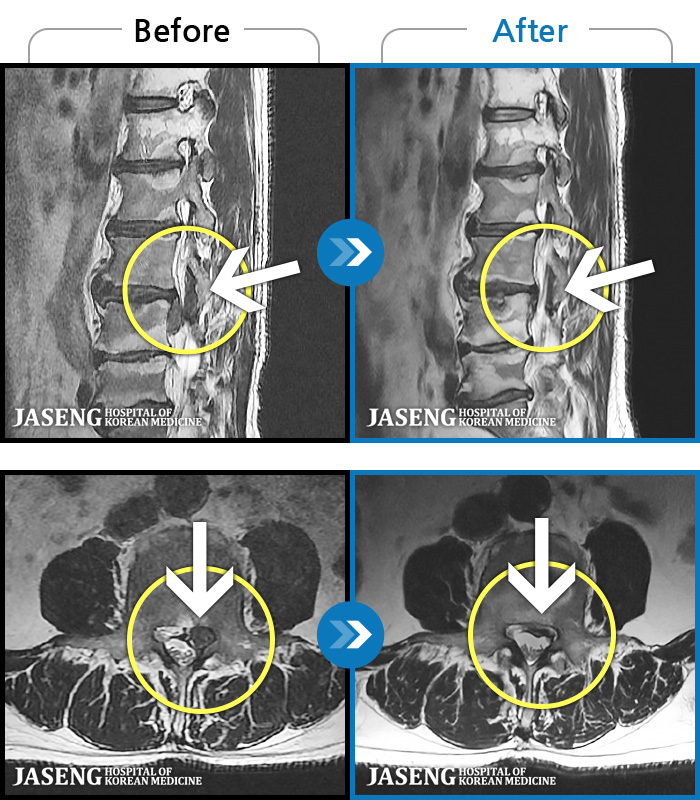

1,251 MRI ũ ʸ Ȯϼ.